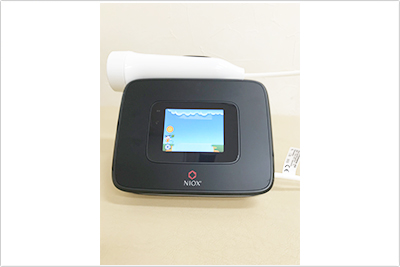

喘息の方は、気道の炎症により、吐いた息の中に含まれる一酸化窒素の濃度(FeNO)が高くなります。数値を測定することで、病状の診断、治療に役立ちます。

お子さまでも、ゲーム感覚で検査することが可能です。